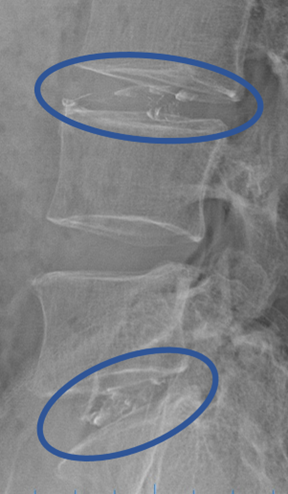

患者様と相談の元、L3/4、5/Sにセルゲル法を施行

DiscoGelを入れた後の画像になります。